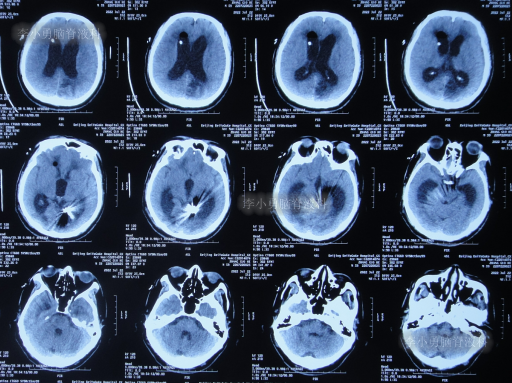

患者于2022年3月16日早晨起床后,无诱因突发头痛,恶心及呕吐,嗜睡,急就诊于当地黑龙江省海伦市某医院,查头颅CT扫描脑出血(片子丢失),因技术有限,120急救车转至上级的黑龙江省哈尔滨某三甲医院,再次复查头颅CT示出血量无明显增多(片子丢失),当天给予脑室外引流术,脑室外引流术后次日查头颅CT示脑出血脑室引流术后(图-1),医生考虑为动脉瘤出血。

图-1:2022年3月17日头颅CT